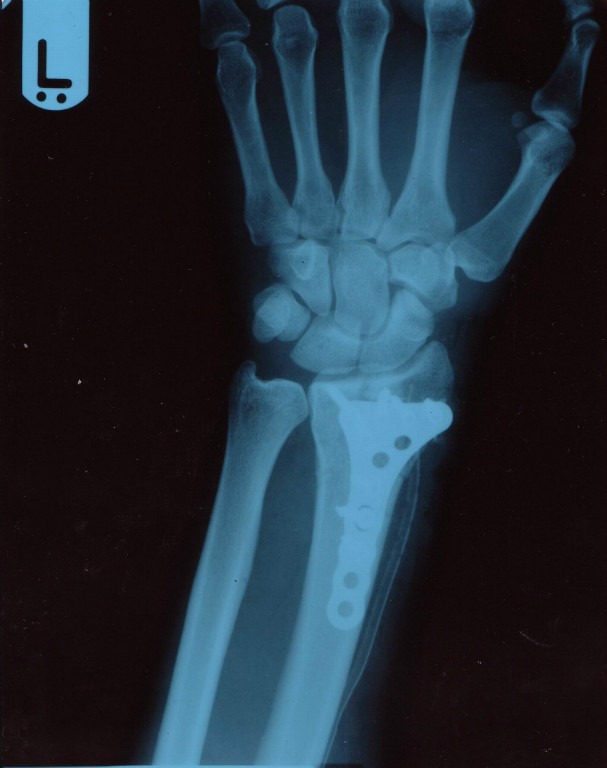

Hart zum Material und noch härter zu sich selbst: